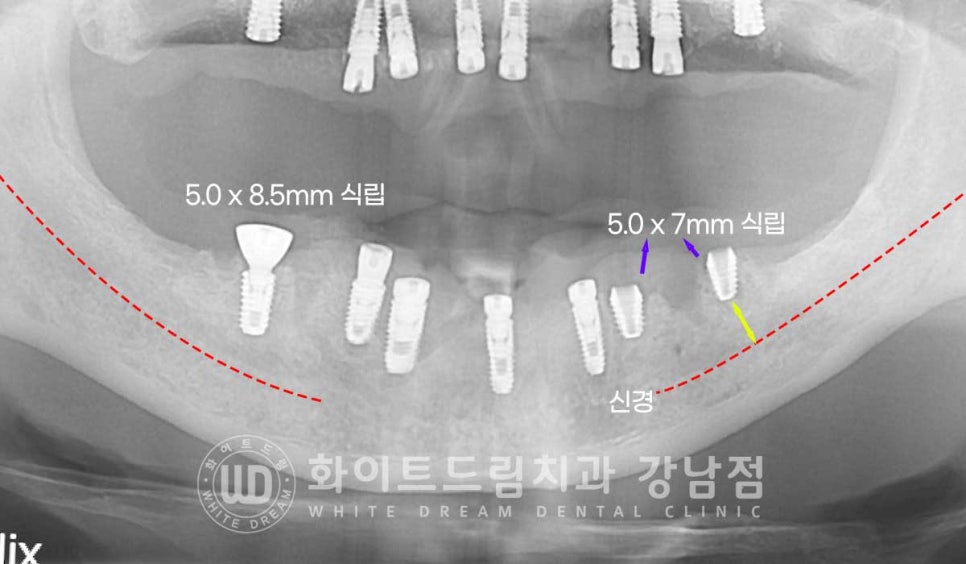

잇몸뼈가 거의 다 녹으신 상태여서 최대한 잇몸뼈가 남아 있는 부위를 찾아서

식립하신 분입니다.

상악 어금니 부위 (16,26번 임플란트)는 상악동 거상술을 동반하였고

대부분의 임플란트는 모두 일반적인 뼈이식, GBR을 동반하여

식립을 진행하였습니다.

환자분처럼 신경관 위쪽으로 남은 잇몸뼈의 길이가 10mm 이내일 경우에는

조금 짧은 임플란트를 선택하여 식립하게 됩니다.